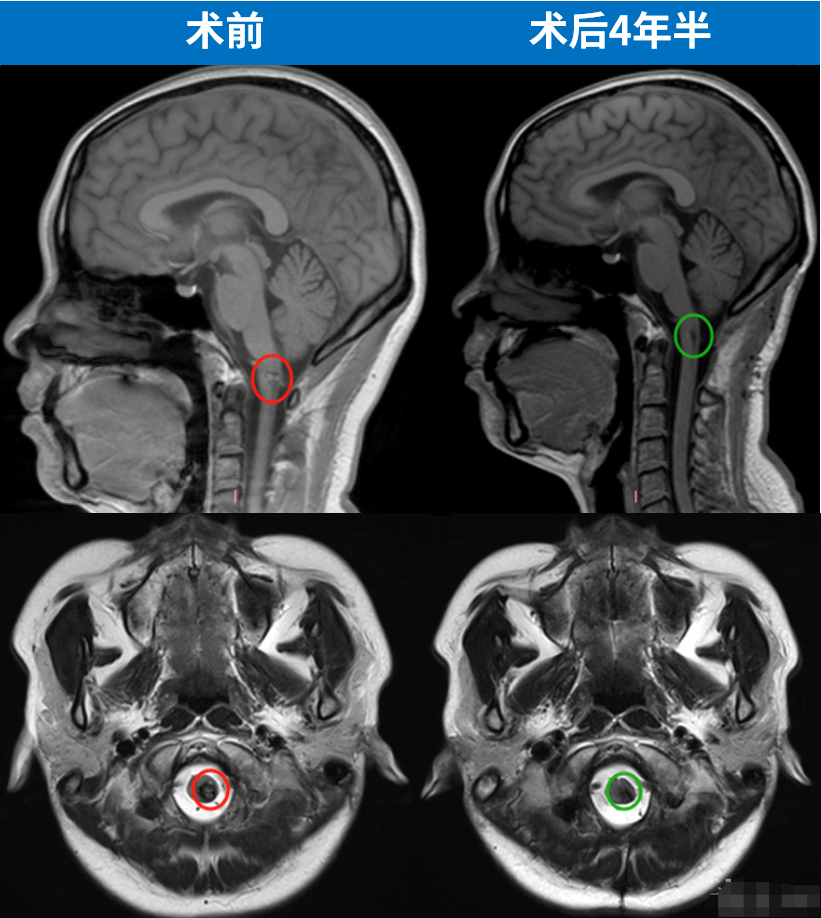

手术圆满成功,王女士在术后次日即拔管下地,两周后顺利出院——曾经被"手术瘫痪"阴影笼罩的王女士,竟以如此惊人的速度回归正常生活。术后MRI明确显示:延颈髓交界处的海绵状血管瘤已完全切除,十余年的致命威胁彻底解除。

更令人振奋的是,2025年7月的最新MRI复查(见图)进一步验证了这一结果:海绵状血管瘤已经被完全切除,术区仅存手术相关的良性瘢痕及含铁血黄素沉积(均为此类术后正常表现),无任何神经功能缺损。而视频中的王女士行动自如、状态饱满。